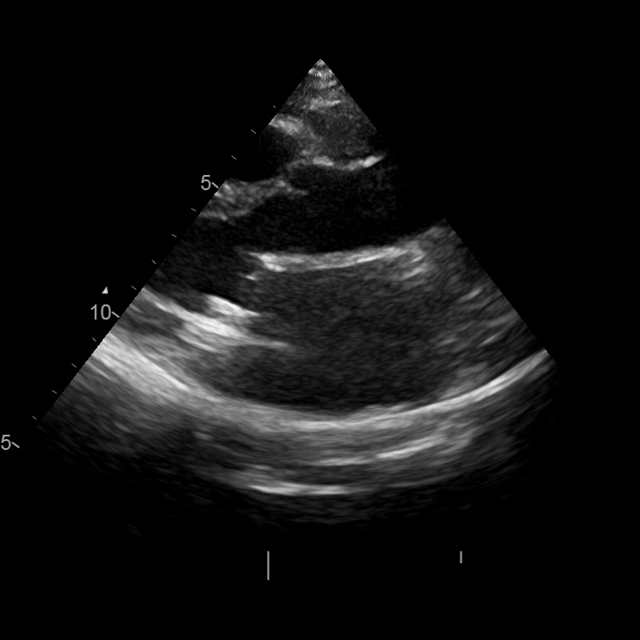

View and measurement extraction

We structure each study to mirror clinical reading: a pretrained classifier assigns standardized views, followed by quantitative measurement extraction. Views are categorized using the American Society of Echocardiography (ASE)–defined classes (mitchell2019guidelines). To extract quantitative parameters, we crop the clinically annotated measurement overlays from the image and transcribe them into structured JSON using Qwen2.5-VL-72B (qwen2.5-VL; Qwen2VL). The resulting fields include chamber dimensions, transvalvular gradients, and Doppler ratios.(Fig. 2a). Extraction fidelity was verified by manual review.

A.5 OCR-Based Measurement Extraction and LLM Caption Validation

OCR-based measurement extraction. We use OCR exclusively to extract measurement name–value pairs from echocardiographic overlays. The initial OCR pass produced 1,232 unique keys, many representing identical measurements with varied naming conventions (e.g., “AV_Vmax” vs. “AV Vmax”) or non-clinical display elements such as gain, velocity scale, or time scale.

To standardize these measurements, we focused on keys appearing more than ten times, yielding 278 candidates. Following clinical reporting practice, we organized all measurements into 11 anatomical categories (LV, LA, RV, RA, MV, TV, AV, PV, SV, pulmonary vein, aorta). Through manual review, these were consolidated into 167 final structured measurements. This curation significantly improves measurement consistency and reduces OCR-related noise.